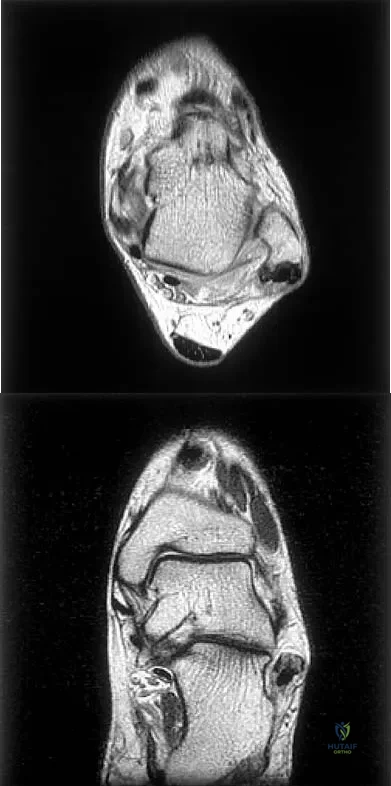

Figures 5a and 5b show axial and coronal MRI images of the left ankle of a patient with lateral ankle pain. What is the most likely diagnosis?

Explanation